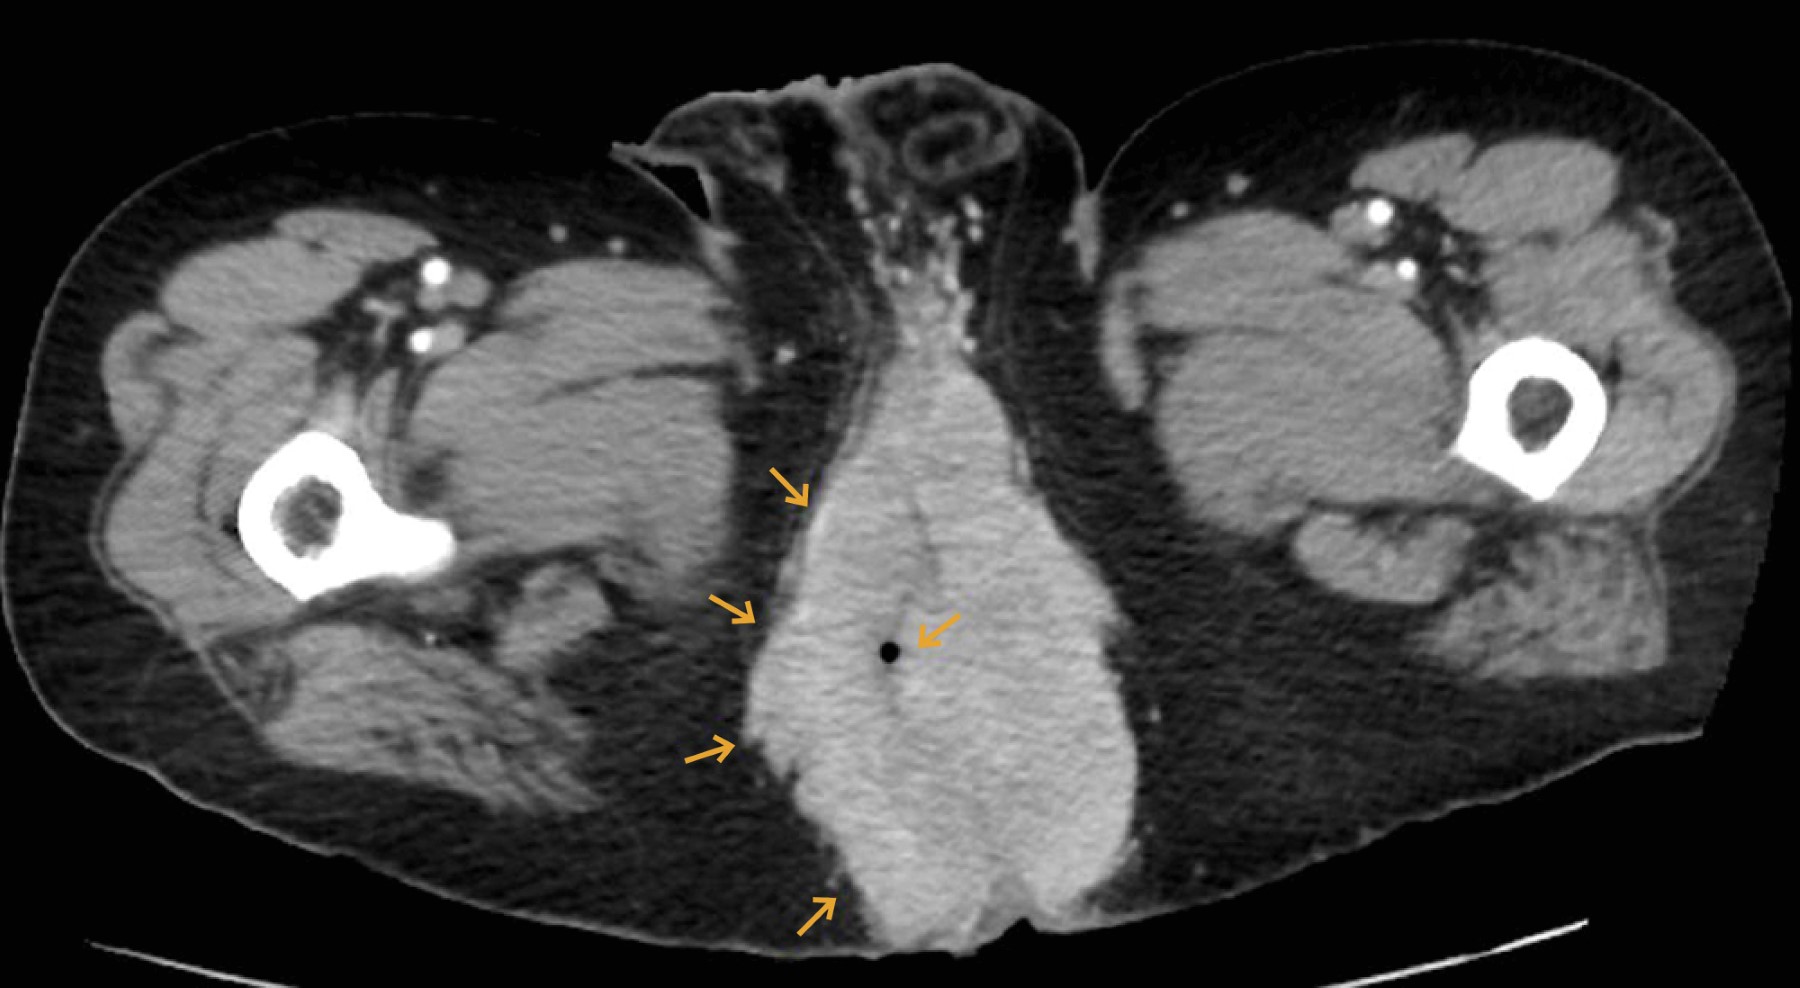

Para complementar la exploración, se solicitó una tomografía abdominopélvica (Figura 2) que evidenció infiltración a nivel de la región perineal con medidas de 15.3 × 9.3 × 11.6 cm de bordes lobulados y mal definidos, así como una colección extensa que afecta el piso pélvico, región perianal y el margen escrotal posterior.

Figura 2